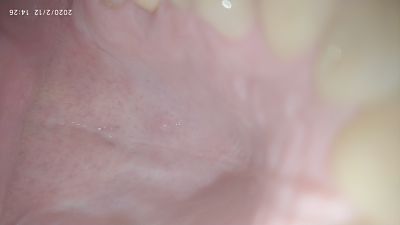

Tengo un granito en el paladar en la zona media-derecha, el caso es que no desaparece y lleva conmigo mas de un mes. Fui al médico hace dos semanas y me dijo que debía de ser una lesión que no me preocupara pero el caso es que no desaparece, a veces parece que se hace mas pequeño pero luego vuelve a aparecer (es como medio grano de arroz) igual y estoy algo intranquilo. ¿Alguien podría decirme que puede ser y como debo de actuar?. Os adjunto algunas fotos. Y Gracias de antemano.